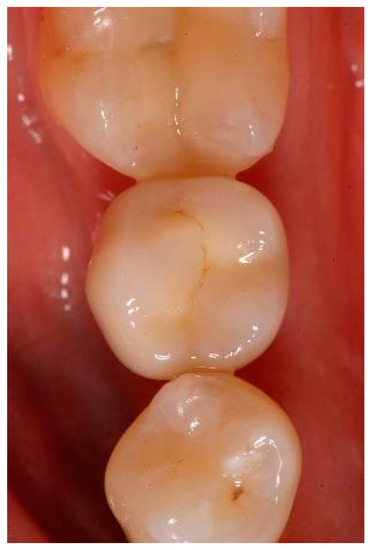

Appendix A. Exemplary Photographs and Radiographs from a Patient at Different Examination Time Points and a Positive Outcome

Patient A:

Figure A1.

Situation after crwon cementation. Occlusal view.

Figure A4.

Clinical situation at the 1-year follow-up. Occlusal view.

Clinical situation at the 3-year follow-up. Occlusal view.

Figure A7.

Figure A10.

Clinical situation at the 5-year follow-up. Occlusal view.